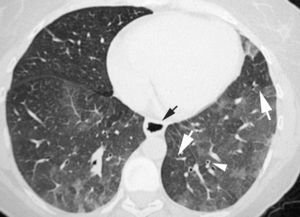

En algunos casos de NINE, como suele suceder en otras neumonías intersticiales, la radiografía de tórax es normal27,28. En la TCAR, lo que caracteriza al patrón de NINE es el «vidrio deslustrado» periférico, en las zonas medias y basales de ambos pulmones (fig. 8)29,30. La panalización ocurre en el 27% de los pacientes, y a medida que progresa la fibrosis, las bronquiectasias y bronquiolectasias de tracción son más visibles7,31. Los hallazgos radiológicos pueden desaparecer por completo tras el tratamiento con esteroides.

El estudio radiológico es normal en el 22% de los pacientes con NID34. La imagen TCAR consiste en opacidades bilaterales en «vidrio deslustrado» de localización simétrica y basal (fig. 9). También se han descrito opacidades lineales y reticulares que en ocasiones son indistinguibles de los hallazgos radiológicos descritos en la NIU35,36.